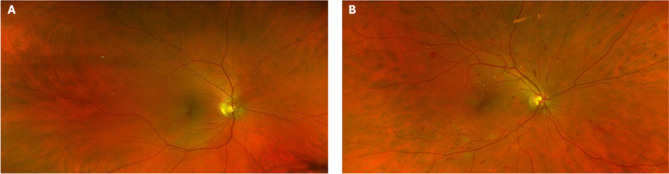

尽管目前的筛查模式、增强的成像方式和治疗方案,糖尿病视网膜病变(DR)仍然是导致工作年龄成年人视力丧失的主要原因之一。DR可导致不可逆的结构性和功能性视网膜损伤,导致视力受损和生活质量下降。鉴于潜在的不可逆的光感受器损伤,在早期阶段进行诊断和治疗将提供避免视力障碍或视网膜病变进展的最佳机会。我们将在此综述目前用于DR评估的结构成像方法及其在疾病初期检测DR的能力。成像工具,如眼底摄影,光学相干断层扫描,眼底荧光素血管造影,光学相干断层扫描血管造影和自适应光学辅助成像将进行综述。最后,我们描述了DR筛查计划的未来和人工智能的引入,作为一种检测糖尿病视网膜细微变化的创新方法。临床试验注册号:n / a。

Despite current screening models, enhanced imaging modalities, and treatment regimens, diabetic retinopathy (DR) remains one of the leading causes of vision loss in working age adults. DR can result in irreversible structural and functional retinal damage, leading to visual impairment and reduced quality of life. Given potentially irreversible photoreceptor damage, diagnosis and treatment at the earliest stages will provide the best opportunity to avoid visual disturbances or retinopathy progression. We will review herein the current structural imaging methods used for DR assessment and their capability of detecting DR in the first stages of disease. Imaging tools, such as fundus photography, optical coherence tomography, fundus fluorescein angiography, optical coherence tomography angiography and adaptive optics-assisted imaging will be reviewed. Finally, we describe the future of DR screening programmes and the introduction of artificial intelligence as an innovative approach to detecting subtle changes in the diabetic retina. CLINICAL TRIAL REGISTRATION NUMBER: N/A.